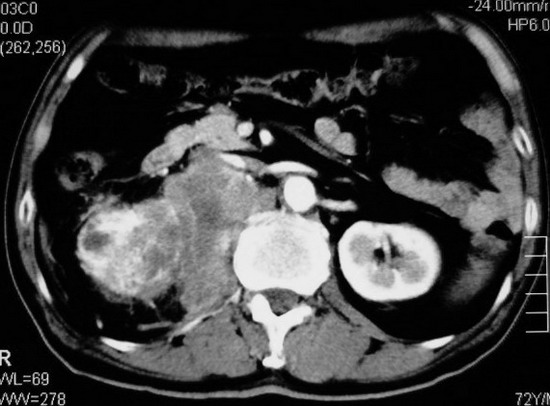

以下是引用杀毒软件在2008-11-17 19:15:00的发言:[br]考虑------右肾癌合并肾静脉---同侧肾上腺受侵可能性大

以下是引用zjzjr在2008-11-17 20:45:00的发言:[br]考虑------右肾癌合并肾静脉---同侧肾上腺受侵可能性大及腹膜后淋巴结转移.